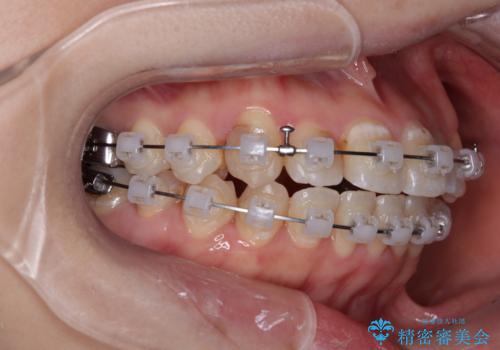

- クリアブラケット

- 上下の歯が非接触であり、八重歯やむし歯を気にして来院された患者様です。

下顎骨の左右偏位はあるものの、上顎骨幅が相対的に狭い状態であったので、奥歯の咬み合わせが非常に乱れていました。

急速拡大装置により上顎骨幅を側方に拡大し、それを利用して八重歯を歯列に納めることにしました。

急速拡大が奏効し、非抜歯矯正にて八重歯を解決することができました。